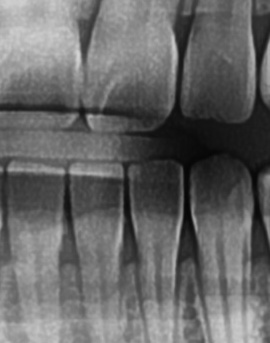

좀더 자세히 원인과 증상에 대해 살펴보면 어금니 뒤쪽은 치아 구조상 칫솔이 잘 닿지 않는 부위라서 음식물 찌꺼기가 남아 있거나 플라그가 쉽게 쌓이게 되는데 치아 사이 공간이 좁고 잇몸이 연약한 부분이라서 세균이 번식하기 쉬운 환경이 만들어지고, 이로 인해 잇몸이 붓거나 염증이 생길 가능성이 커질 수 있었어요

처음에는 가볍게 붓고 불편한 정도지만, 점점 심해지면 통증이 발생하거나, 잇몸이 붉어지고 단단해지면서 눌렀을 때 고름이 나오는 경우도 있어요. 이런 경우 단순한 염증이 아니라 치주염으로 발전할 가능성이 있기 때문에 치과에서 정확한 검진을 받는 것이 필요한 거예요

어금니 뒤 잇몸 부음의 문제는 사랑니가 원인이 되는 경우도 많은데 사랑니는 특히 현대인들의 경우 제대로 나오지 못하고 매복되는 경우가 많으며 완전히 나오지 않은 사랑니는 잇몸 속에서 자라면서 주변 잇몸을 자극할 수 있고, 일부만 노출되면 음식물이 끼면서 염증이 생기기도 하며 특히 어금니 뒤쪽 잇몸이 붓고 지속적으로 불편함을 느낀다면 사랑니로 인한 염증을 의심해 볼 수 있어요. 사랑니로 인한 문제의 경우 단순한 소염제나 구강 세정제로 해결되지 않고, 사랑니를 발치해야 잇몸 염증이 해결되는 경우가 많이 있어요

가장 주의해야 하는 문제 중에 치주염이 진행되면 어금니 뒤쪽뿐만 아니라 전체적인 잇몸이 약해질 수 있어요. 치주염은 치아를 둘러싸고 있는 조직이 손상되는 질환인데 특히 잇몸이 자주 붓거나 피가 나는 경우에는 치주염이 진행되고 있는 신호일 수 있기 때문에 단순한 잇몸 붓기로 넘기지 않는 것이 좋으며 치료를 받지 않으면 결국 치아를 지탱하는 뼈가 약해지고, 심한 경우에는 치아가 흔들리거나 빠질 수도 있었어요.